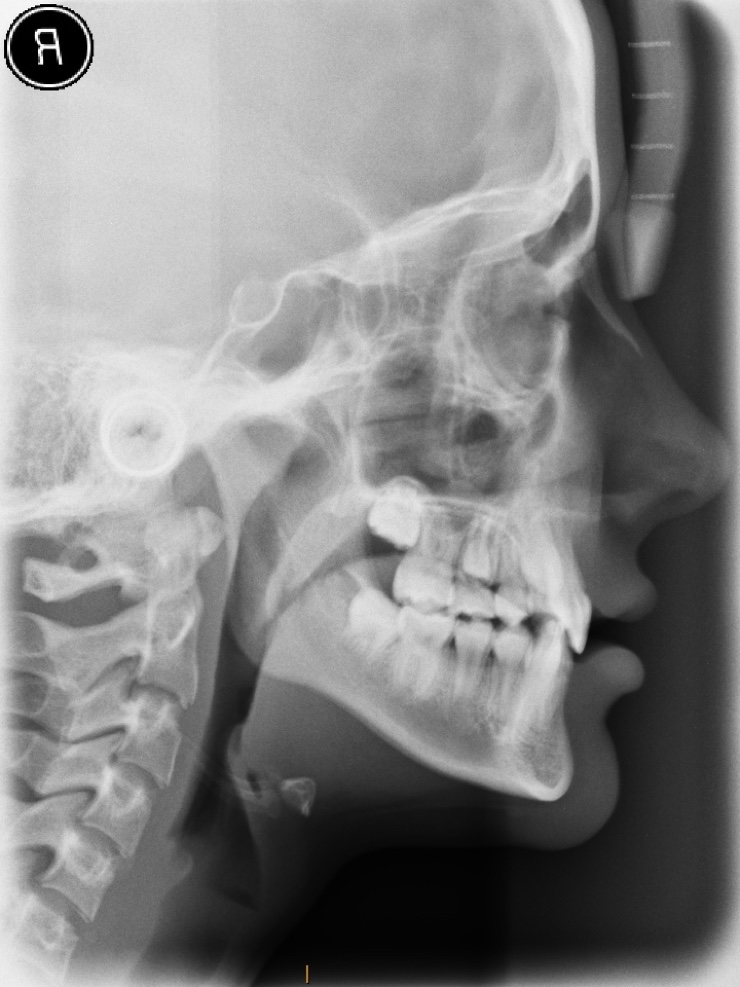

Lateral Cephalometric X-ray of the head

Orthopantomograph X-ray of the teeth and jaws